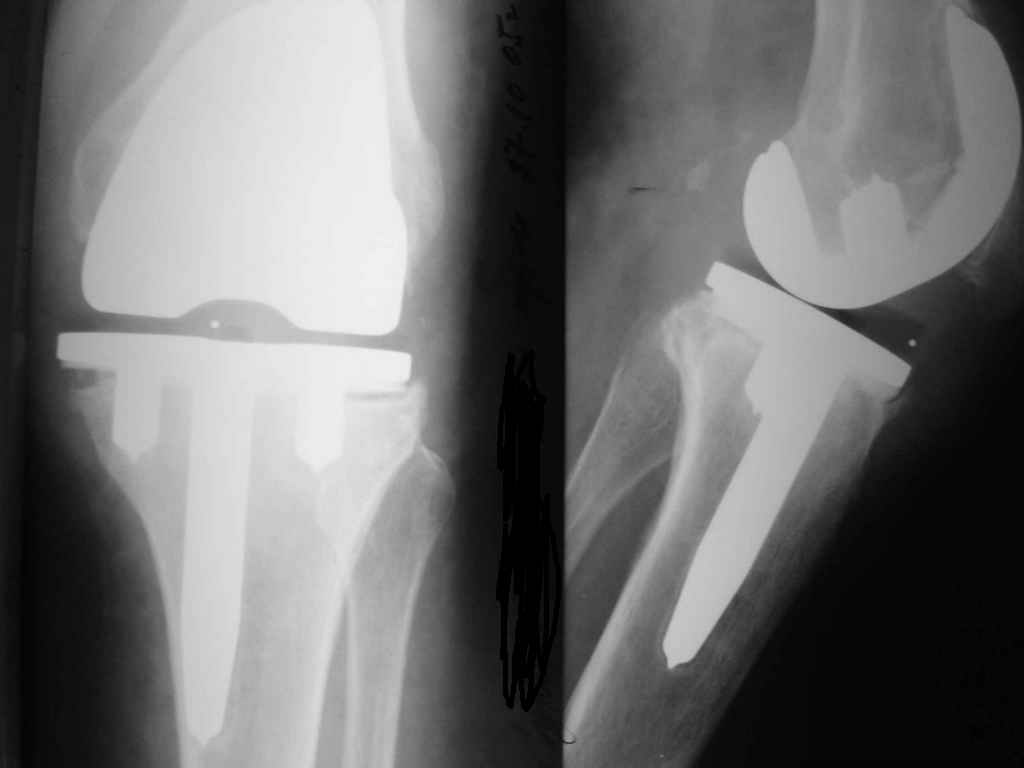

Уважаемые коллеги. Пациентка 65 лет соматически сохранна 6,5 месяцев назад выполнено замещениеколенного сустава интегральным эндопротезом Фримана Самуэльссона - цемент, по поводу ДОА. Послеоперационное течение с длительным субфебрилитетом. Местно без особенностей и выписана домой на 28 сутки с обьемом движений в колене 90 град. с частичной опорой. Дома отмечала субфебрильную лихорадку. Живет в небольшом поселке далеко от цивилизации. Контрольный осмотр в 3 месяца особых клинических проблем лечащий врач не нашел. Однако рентгенологически отмечены зоны остеопороза вокруг компонентов, на которые не обратил внимание. С 4 месяца отметила ухудшение - отек в колене, ограничение движений и боль. Лечилась у местного врача-хирурга (нестероиды и местно мазилки) - без эффекта. Обратилась только в 6,5 мес. Движения в суставе 20 град, отечность колена, выпот по УЗИ. Боль неопределенная, ходит с тростью. Лихорадки нет, в ан крови СОЭ 36 остальное норма, острофазовые тесты СРР повышен вдвое = 12 (при норме 6) Ревмотест - норма..Пункция - посев - роста не дает. Пробовали артроскопию - артрофиброз. Трудности осмотра из-законтрактуры и спаек. Рентгенограммы в динамике - в приложении (динамика с ухудшением). Вопросы:1. Инфекция? или остеопения местная? 2. Ревизия или подождать и полечить остеотропами? Благодарю заранее за любой совет. А Рыков. Хабаровск.

Показание к ревизии - нестабильность протеза (его компонентов) В приведённом Вами случае на Рг очевидная зона резорбции вокруг тибиального компонента следствие этого его нестабильность. Наиболее вероятна вялотекущая инфекция( судя по показателям крови и клиническим проявлениям: отек, боль, выпот и как следствие - ограничение функции)

Надеяться на чудо, что тибиальный компонент *самостабилизируется* едва ли приходится, наоборот, отсрочка ревизии усугубляет околопротезную деструкцию и ревизия технически усложняется за счет дефицита опорной кости, придётся изобретать с графтами и спейсерами, а это дополнительные расходы (в данном случае время - деньги :-))